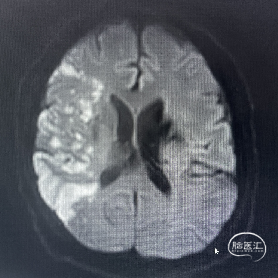

辅助检查:CT见右侧基底节区及右顶叶低密度病灶。

辅助检查:DWI:右侧大脑半球脑梗死灶;MRA检查:右侧大脑中动脉闭塞。